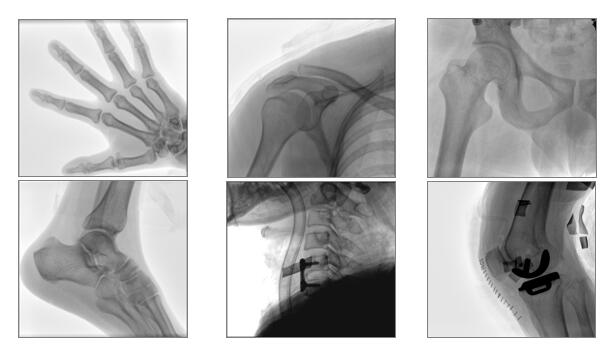

【產(chǎn)品臨床圖片】